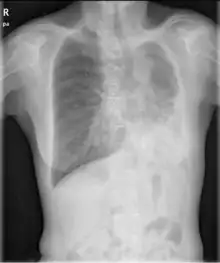

| Chest radiograph of a woman with unilateral pulmonary agenesis | |

- Chest X-ray is effective in detecting the traits of lung herniation.[1] The unaffected side of lung tends to undergo hypertrophy, and move towards the empty space in the chest wall on the opposite side.[1] This herniation could be indicated by fluoroscopy.[1] With age increasing, the herniation progresses and ease its detection.[1]

- Electrocardiogram is useful in detecting dextrocardia, a possible outcome when agenesis is present on the right lung.[1] With empty space in the chest wall, the heart rotates in clockwise direction, shifting the location for apex beat occurrence.[1] Hence cardiac physical examination also helps as heart sounds is heard best at right chest with dextrocardia.[1][4] In the condition of left side agenesis, heart sounds will appear to be louder than normal.[1][4]

- Chest asymmetry, as a possible trait for pulmonary agenesis, is found to be more obvious in adult patients, especially in males.[4] Breast development in females tends to make it less obvious for the observance of asymmetry, though it could still be indicated by a more conical shape and slightly higher location of the breast on the affected side.[4]